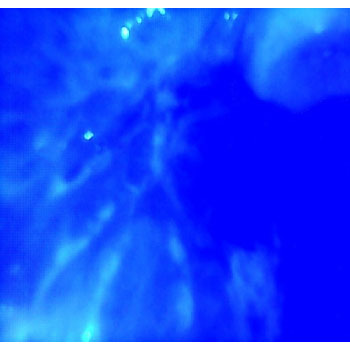

clinical Image and Image of the lesion Under the influence of Blue light, we can appreciate the difference in the extent of the lesion under white light and blue light. The blue light used with low intensity.

Clinical Image and Blue light image with High intensity of light, Both Images are filtered for better appreciation